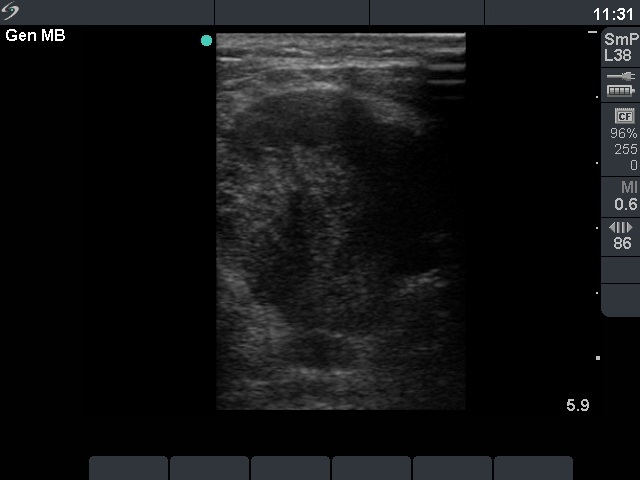

Ultrasonography: there was a hypoechogenic, inhomogeneous nodule occupying almost the entire left thyroid. The nodule spread substernal. The lesion contained microcalcifications and had irregular borders. The intranodular blood flow was decreased.